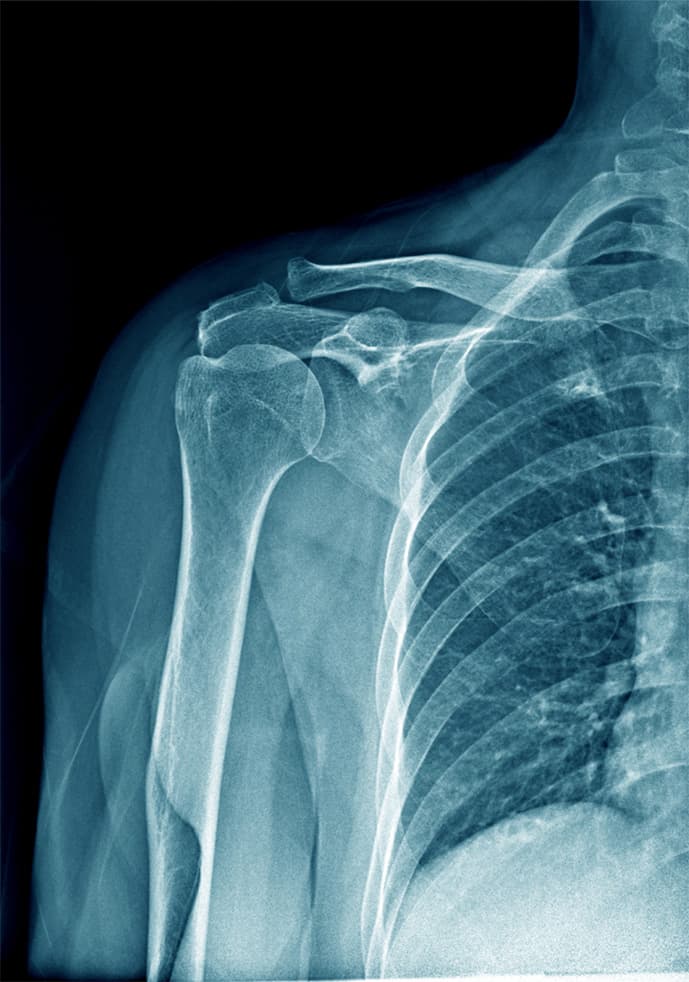

La patologia artrosica della spalla, nota anche come omartrite, è un processo degenerativo che colpisce l'articolazione scapolo-omerale. Frequentemente correlata all'età avanzata, questa condizione può manifestarsi anche in seguito a traumi o usura meccanica.

L'instabilità di spalla rappresenta una condizione in cui la spalla mostra una propensione a dislocarsi dalla sua posizione anatomica normale, sia in modo completo (lussazione) che parziale (sublussazione).

Nei pazienti affetti da instabilità, potrebbe essere necessario sottoporsi a un intervento di capsuloplastica artroscopica o, nei casi più complessi, all'intervento di stabilizzazione secondo Latarjet.